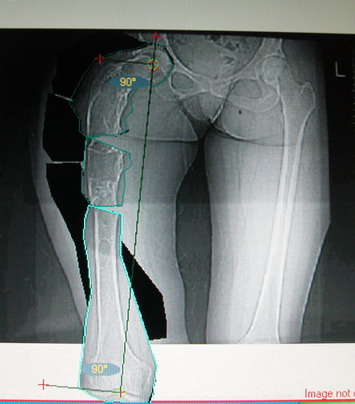

На мой взгляд, для того, чтобы правильно исправить данную деформацию, необходимо обследование больного, которое должно включить в себя, помимо осмотра: 1. Рентгенограммы ( передне-задние и боковые)нижних конечностей на всю длину стоя . 2. Компьютерная томография для измерения длины нижних конечностей. 3. Комьютерная томография тазобедоенных, коленных и голеностопных суставов для измерения углов антеверсии тазобедренных суставов и ротации голеней. Это тот минимум, который должен входить в предоперационное обследование каждого больного с тяжёлыми формами деформаций конечностей.

Поскольку в данном случае имеется дело с довольно большой деформацией с укорочением, одномоментная её устранение с внутренней фиксацией, чревато с одной стороны неправильной коррекцией, с другой, нейроваскулярными осложнениями.

Моё мнение, что двойная остеотомия бедра с аппаратом Илизарова + Гексаподный механизм, или Тэйлора, В данной ситуации является методом выбора. Я очень извеняюсь за качество прилагаемых снимков, в которых я постарался отразить разницу междe одной и двумя остеотомиями бедра.

jo> отразить разницу межде одной и двумя остеотомиями бедра.

Скорее всего, второй уровень может оказаться нелишним лишь при переходе с аппарата на интрамедуллярный стержень. И его не поздно будет пересечь именно в момент введения гвоздя, если будет угроза перфорации стенки канала.

Собственно сустав не беспокоит, объем движений полный. По скиаграммам получается, что достаточно одной остеотомии на вершине деформации, чтобы восстановить длину и вывести коленный сустав в нужное положение.

Т.к. укорочение 7 см, то начинать будем с соеотомии и коррекции аппаратом. Спасибо